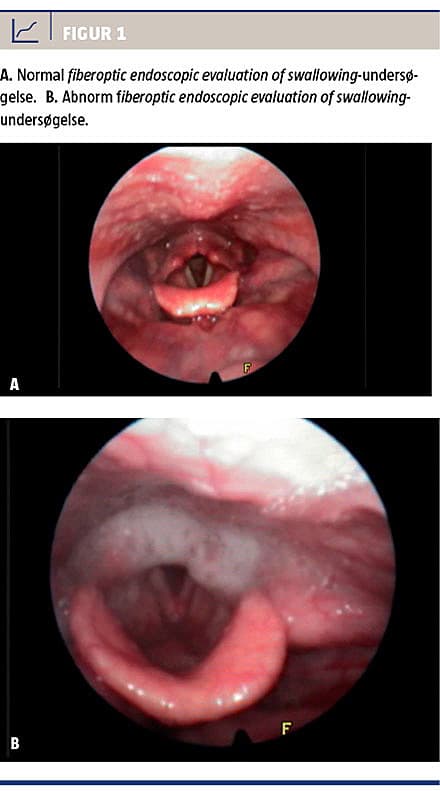

FEES-metoden er en endoskopisk undersøgelse, hvor man visualiserer den bløde gane, larynx og hypopharynx før og efter synkning. Umiddelbart kan man få mistanke om synkeinsufficiens, hvis der ses retineret og større mængder sekret over stemmelæberne, eller hvis sekret har penetreret disse [3, 24] (Figur 1). Med FEES kan patientens synkefysiologi kortlægges, aspiration kan visualiseres, og undersøgeren kan kortlægge, hvornår i synkeprocessen patienten aspirerer [24]. FEES gør det muligt at vurdere både de motoriske og de sensoriske komponenter i synkeprocessen og samtidig beskytte luftvejene [21]. Desuden kan FEES gentages så ofte som nødvendigt, hvorfor man løbende kan vurdere synkeinsufficiente patienters evne til at mobilisere sekret [22]. FEES kan foregå bedside, hvilket gør den særligt velegnet i intensiv regi, hvor patienterne ofte ikke er flytbare eller koorporable. Undersøgelsen kan suppleres med indgift at farve per os (Figur 2). FEES kan videodokumenteres og er sikker og godt tålt af patienterne [3, 15, 21, 24].